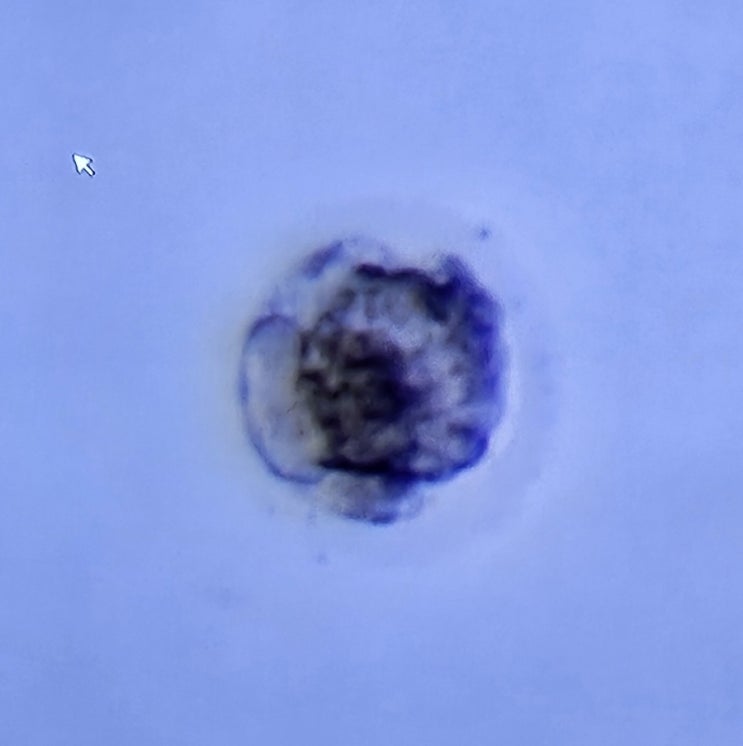

평촌마리아 시험관 성공! 6주 1일차 아기집 초음파, 증상

평촌마리아 시험관 성공! 6주 1일차 아기집 초음파, 증상 드디어 아기집 초음파 보러 가는 날~! 남편도 연...

평촌마리아 시험관 동결이식 2차 : 중급 포배기배아 이식 비용, 후기

평촌마리아 시험관 동결이식 2차 : 중급 포배기배아 이식 비용, 후기 2024년 12월 20일 평촌마리아 동결배...